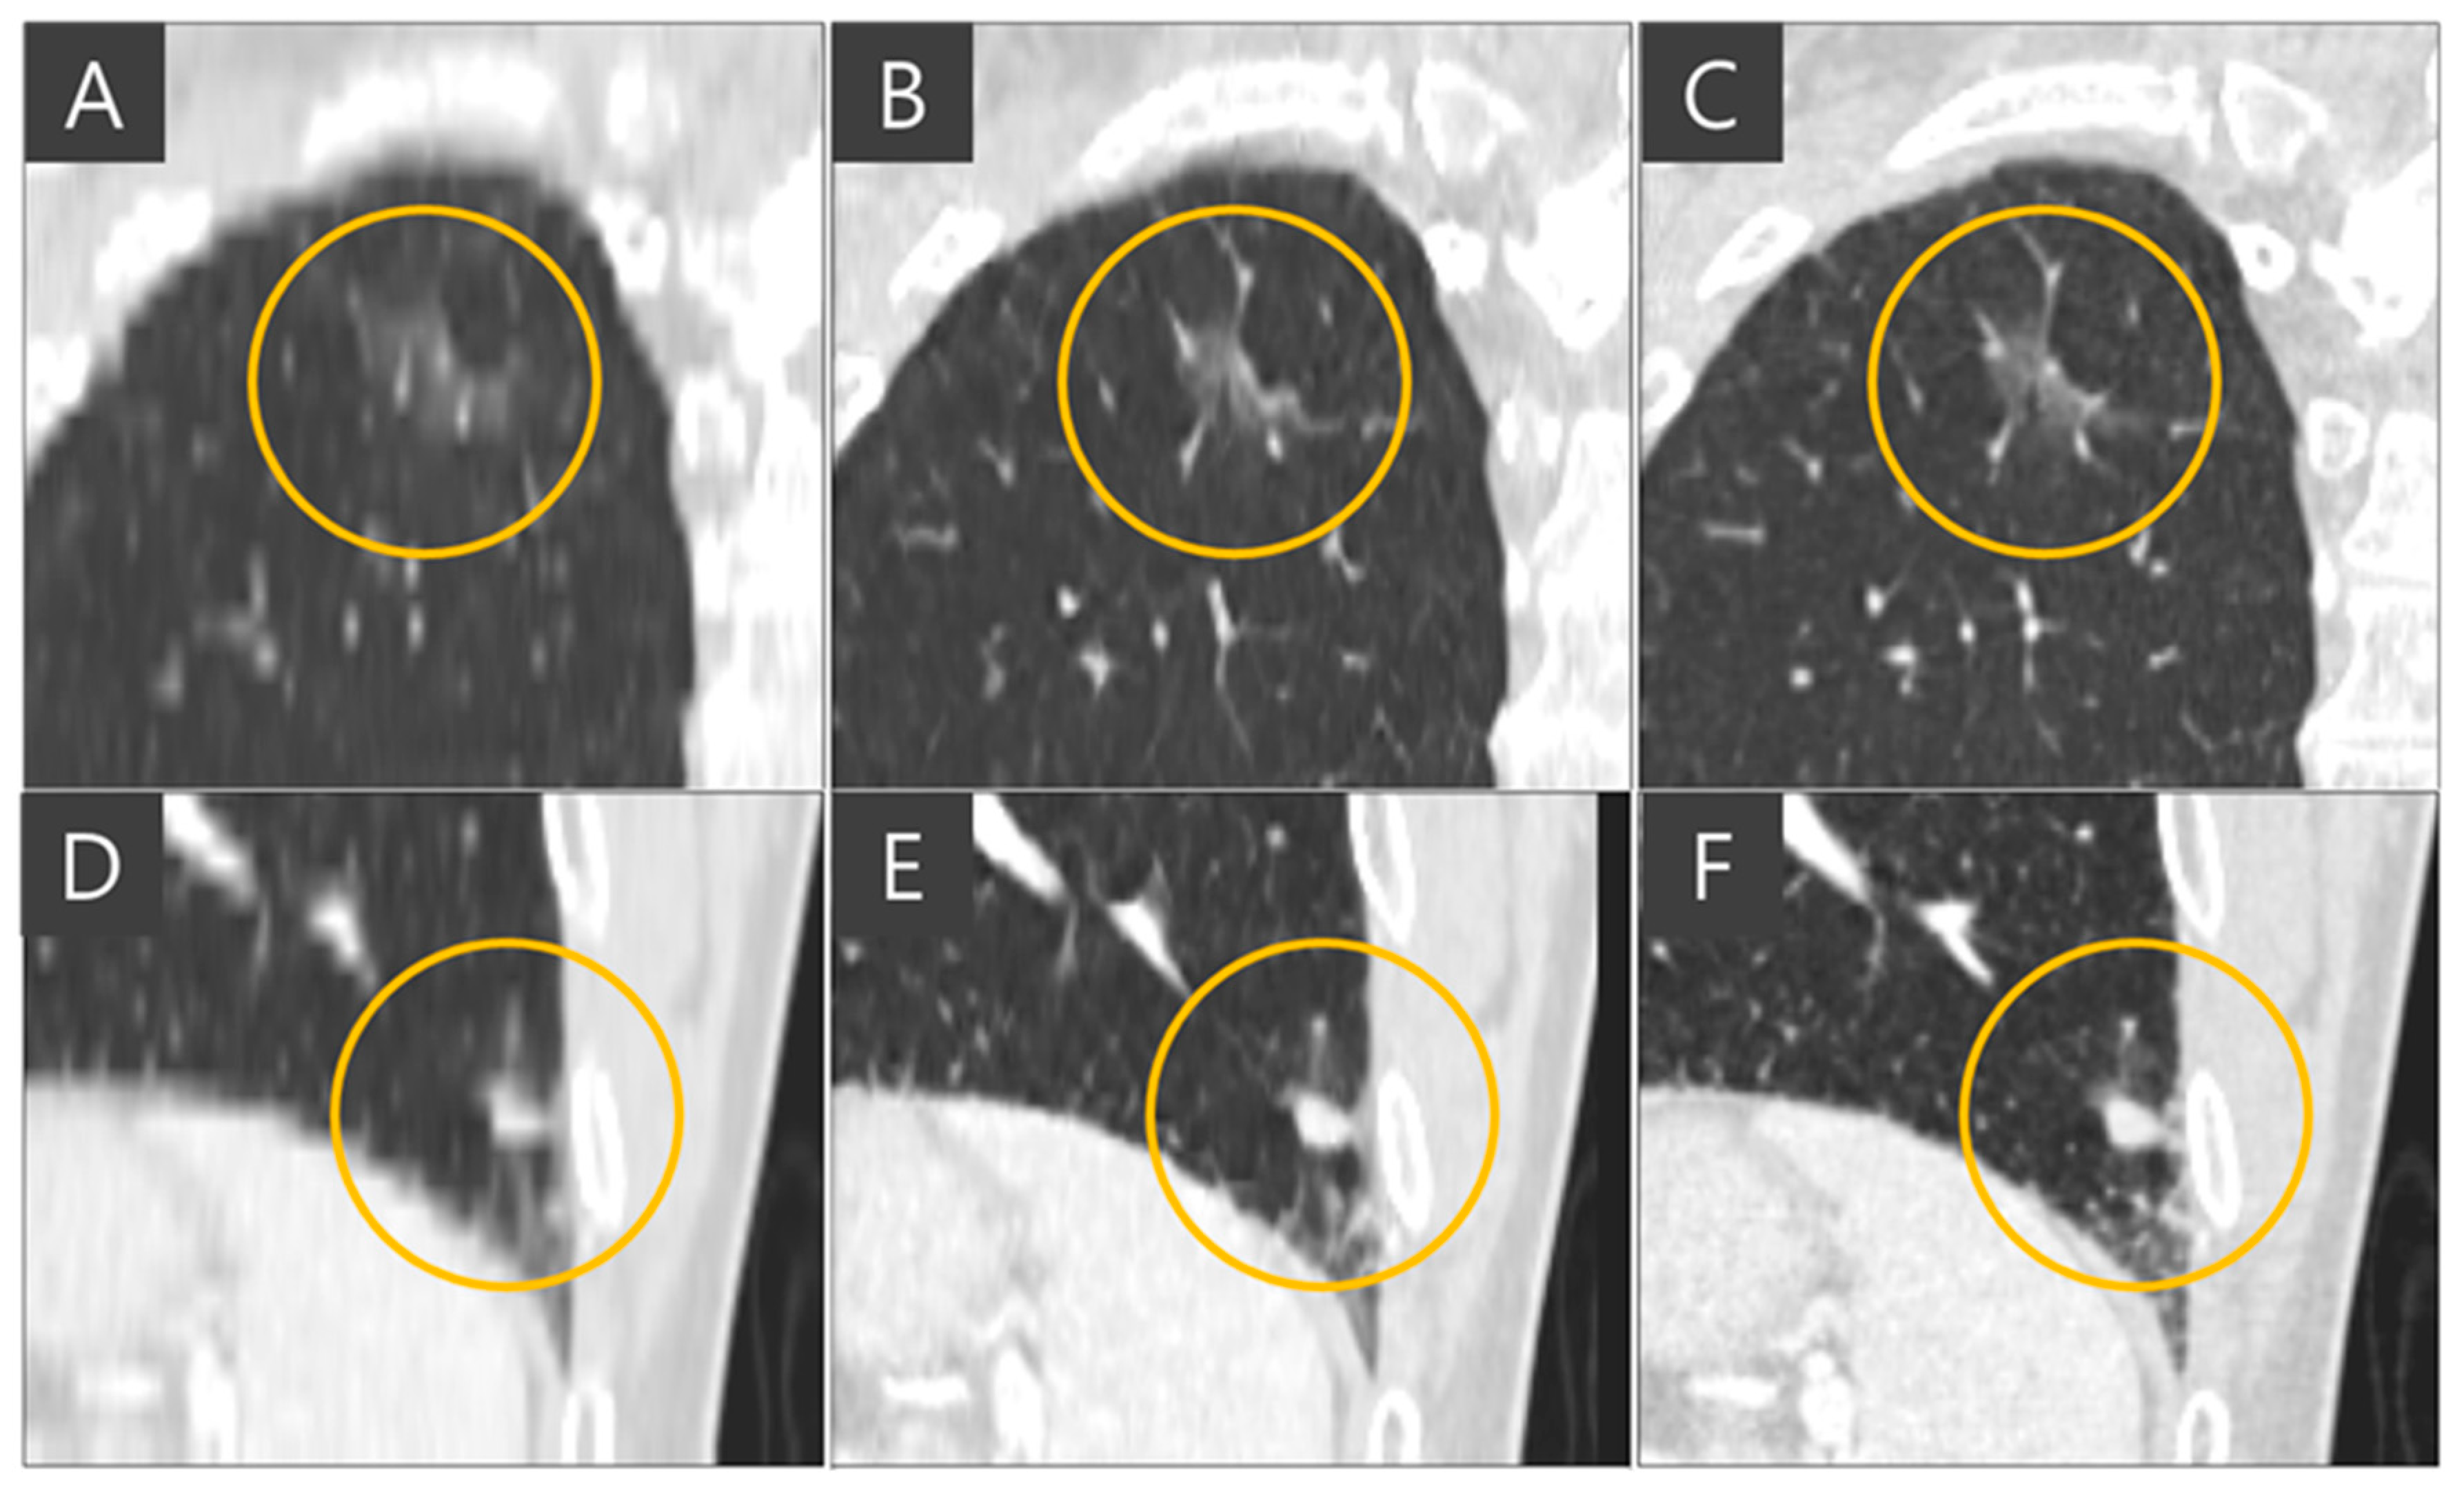

The representative coronal views of thick-slice, generated thin-slice, and ground truth thin-slice CT images are presented in Figure 4. The thick-slice CT image exhibits staircase artifacts, unidentifiable fissures, and blurred lung vessels, whereas the generated thin-slice CT image quality is comparable to that of the ground truth thin-slice CT image. Visual inspection of GGN and solid nodules in each image type reveals clearer distinctions. In Figure 5, the GGN in the thick slice CT image has indistinct boundaries, making accurate segmentation and volume estimation challenging. In contrast, the GGN in the generated thin-slice CT image closely resembles that in the ground truth thin-slice CT image, facilitating accurate assessment. The Likert scale scored 1, 4, 5 on the visibility of fine lung structures, 1, 4, 5 on nodule margin delineation, and 1, 4, 5 on visibility of GGN/subsolid nodule component for thick-slice, generated thin-slice, and thin-slice CT, respectively, by both radiologists. Similarly, for solid nodules, the thick-slice CT image lacks sufficient image quality for precise volume measurement, whereas the solid nodule in the generated thin-slice CT image exhibits adequate quality for accurate segmentation, mirroring the ground truth. The Likert scale scored 1, 4, 5 on the visibility of fine lung structures and 1, 4, 5 on nodule margin delineation for the thick-slice, generated thin-slice, and thin-slice CT, respectively, by both radiologists.

Figure 5. GGN circled in (A) thick-slice, (B) generated thin-slice, and (C) thin-slice CT images and solid nodule circled in (D) thick-slice (E) generated thin-slice, and (F) thin-slice CT images.